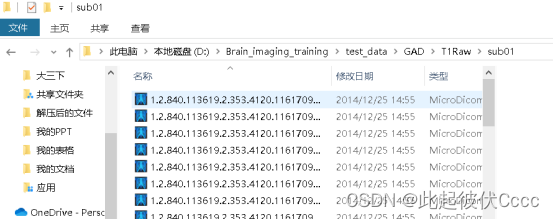

每个subxx文件存放被试的.dcm图像文件: